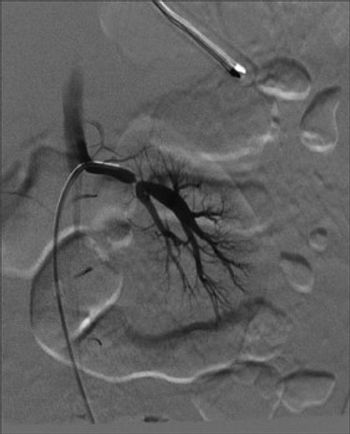

Radiographically occult wrist fractures, polypharmacy, invasive infection and hepatocellular carcinoma in HIV-infected patients. . . . here: a variety of subjects for you to test your clinical range.